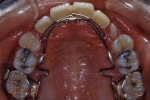

ベッグタイプ

抜歯症例の場合、抜歯した部分が後戻りして隙間が生じるのを防止するため歯並び全体を包み込むように、ワイヤーが取り囲むデザインの保定装置が使用される場合があります。このデザインをベッグタイプのリテーナーと言います。